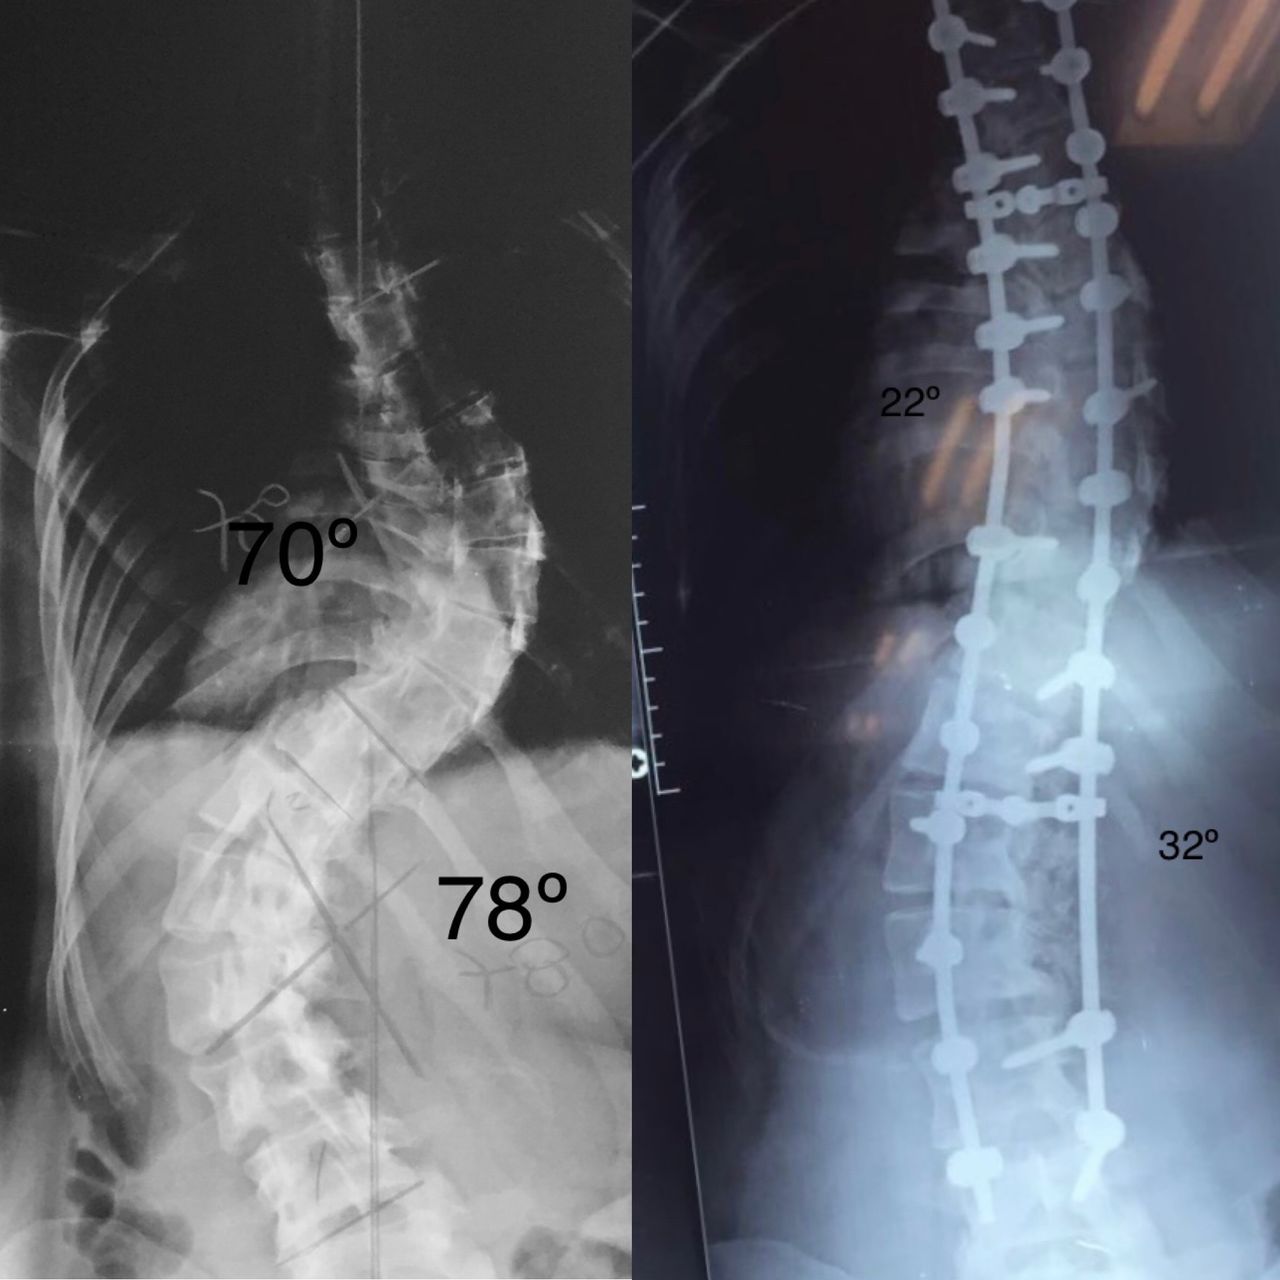

Doença De Scheuermann

A doença de Scheuermann ocorre normalmente meninos em fase de estirão de crescimento, e se apresentam com dor e aumento da cifose (corcunda). Ela decorre de tendência genética, onde há uma inflamação nos discos e vértebras da coluna, que começa, a se deformar. Quando diagnosticada precocemente, pode ser tratada clinicamente com exercícios posturais e colete, eventualmente. Em caso onde há progressão da curva, indicado cirurgia para correção e estabilização da doença.